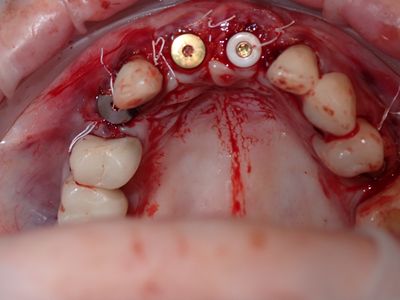

NSankhyan - immediate 13, impls 1121 and 25 with grafting

13 exo, loss of labial plate, implant placed buccal region grafted with sticky bone and collagen membrane soaked in prf fluid. 11/21 limited Labial-palatal width of bone, ridge split to 5mm, osteotomies prepared to about 2mm, remainder with densah drills, implants placed with ample bone, buccal grafted with same sticky bone. densah drills used for apical portion of 25 implant, soft bone, implant placed